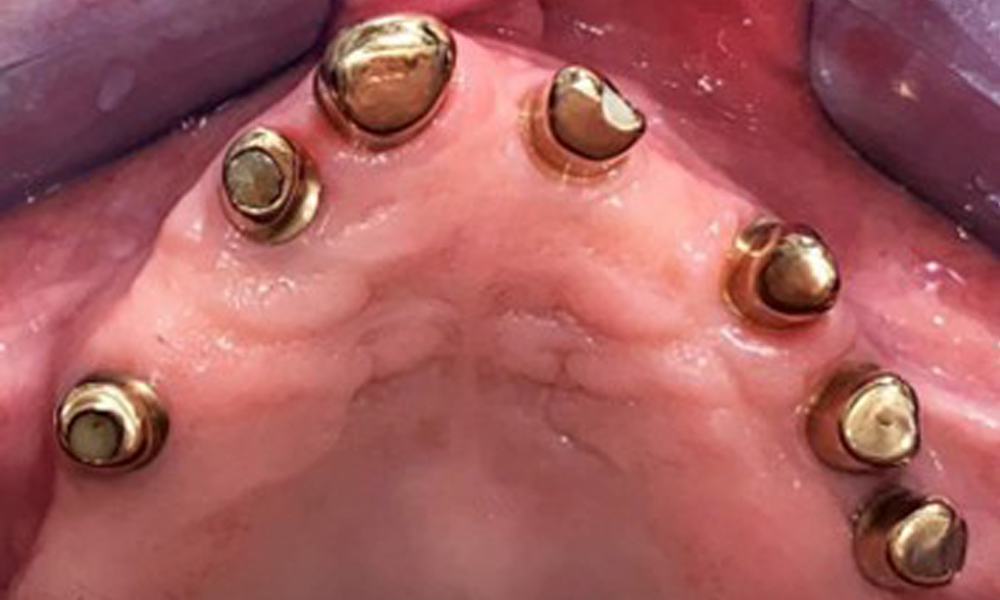

Occlusal view of the mandible.

Fig. 4: Occlusal view of the mandible.

The dental findings are as follows: Combined removable implant and tooth-supported telescopic prostheses on implants 15, 13, 21, 23, 24, 25 and tooth 11 (Fig. 1, Fig. 2, Fig. 3). The patient was fitted with a fixed mandibular denture. Adequate bridges were present over 37 to 34 and 45 to 47 (Fig. 4), the crown margins were intact and there were no active caries. A composite filling with a marginal gap was present on tooth 43. There was mandibular gingival recession, exposing 1 to 3 mm of root surface. This also applies to 11.